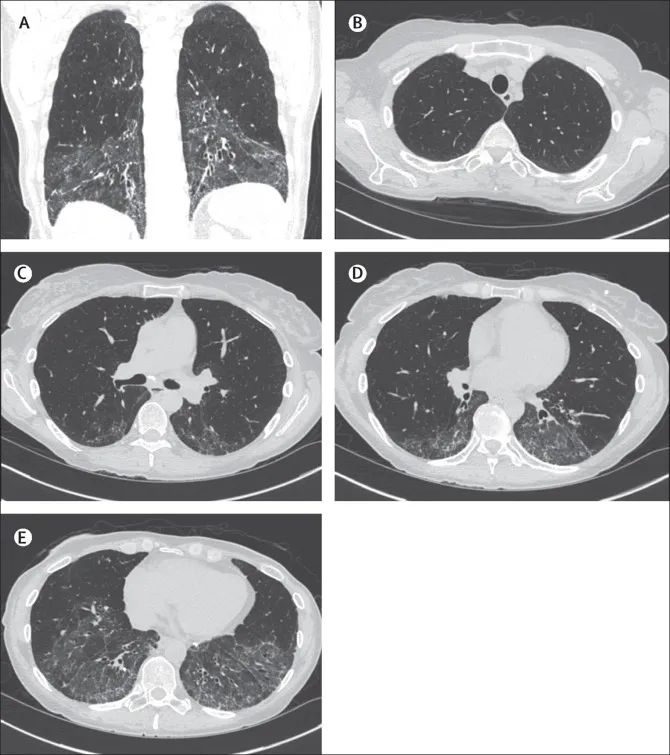

SSc-ILD的影像学

HRCT上最常见的影像学表现是非特异性间质性肺炎,在80%以上的SSc-ILD患者中可见(图A-E)。特征是成片状磨玻璃样改变,尤以胸膜下区域明显。在SSc-ILD患者中,只有10%的患者存在明确的间质性肺炎模式,没有磨玻璃样变但伴有蜂窝样变。